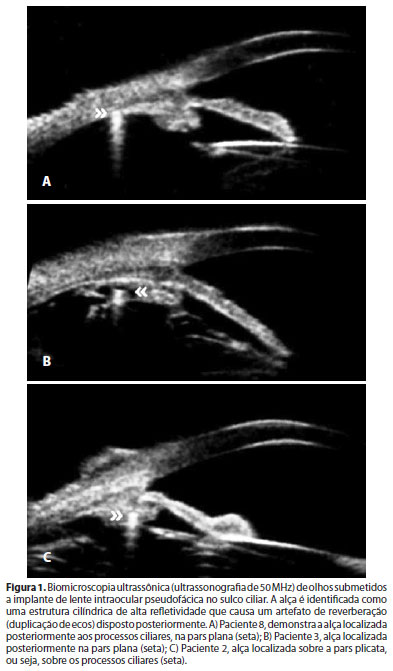

Na tabela 3, que mostra a localização das alças das lentes, pode-se observar que em 3 (27,2%) olhos ocorreu assimetria do posicionamento das alças: 2 (18,1%) olhos com uma alça no sulco ciliar e a outra alça na pars plana e 1 (9%) olho com uma alça no sulco e a outra no corpo ciliar (Figura 1). Nos 8 (72,7%) olhos restantes, ambas as alças estavam simetricamente posicionadas no sulco ciliar.

A tabela 4 mostra os achados do exame oftalmológico. Na biomicroscopia em lâmpada de fenda não foi observada a presença de "flare" e/ou células na câmara anterior em nenhum dos olhos. As alterações irianas observadas em 5 (45,5%) olhos foram decorrentes do trauma cirúrgico e caracterizaram-se por áreas localizadas de atrofia do bordelete ou do estroma iriano. A descentração da LIO foi observada em 2 (18,1%) olhos (Figura 2). A PIO média encontrada na série foi de 15 ± 2 mmHg, sendo que um olho necessitou de medicação antiglaucomatosa para controle da mesma. Em todos os olhos (n=11) foi observada uma hiperpigmentação do trabeculado, à gonioscopia. Na avaliação de fundoscopia, não foram observados rotura periférica de retina e/ou edema de mácula.